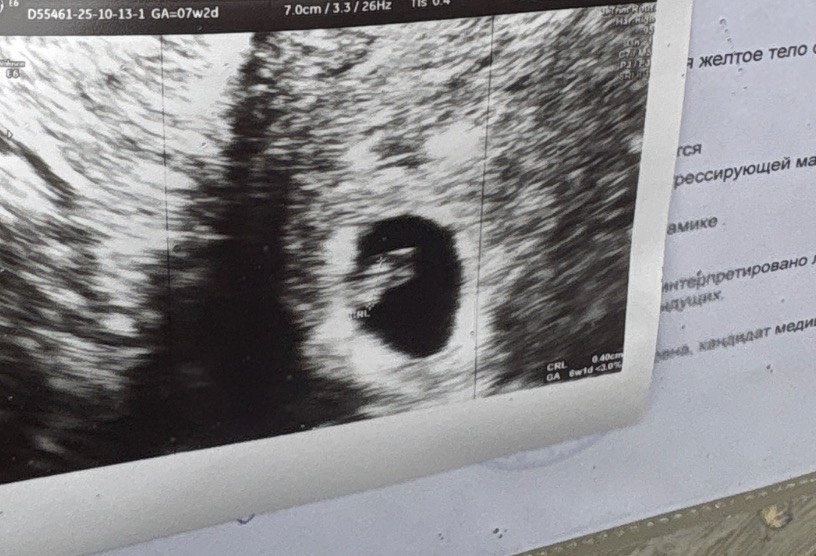

Сегодня была на первом узи.

Срок тютелька в тютельку по кд и овульке, человек есть, сердце бьется, повидались 🥰